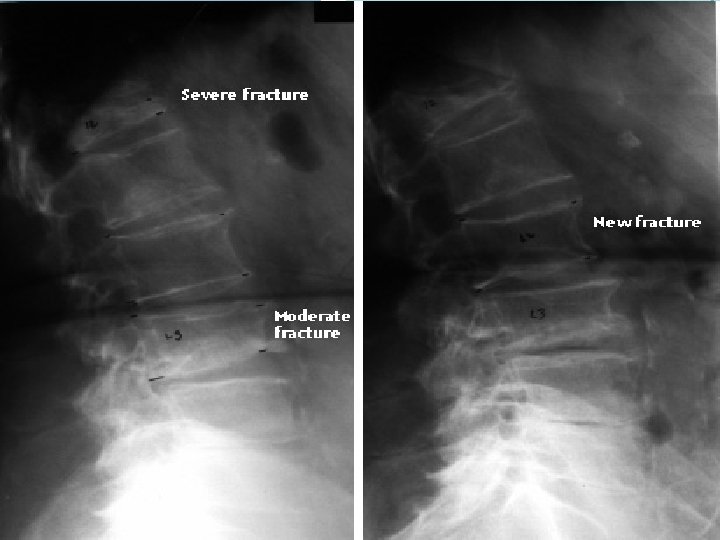

Tanı �Radyografi; �Osteoporozda rutin olarak torakal ve lumbosakral vertebraların anteroposterior ve lateral grafileri, pelvisin anteroposterior grafisi çekilmelidir. �Kemik kaybı %25‐ 30’a vardıktan sonra ancak radyolojik olarak belirlenebilir. �Bu nedenle tanıda duyarlı değildir fakat olası kırıklar ve tedavi izlemi açısından değerlendirilmlidir.

Tanı �Vertebra; �Lateral vertebra grafilerinde, vertebral yükseklikte %20 den fazla (2 cm) kısalma � Evre 1 (hafif) %20‐ 25 � Evre 2 (orta) %25‐ 40 � Evre 3 (şiddetli) >%40